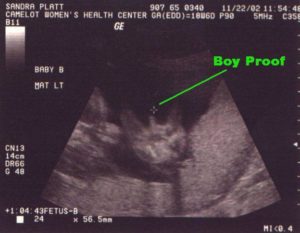

Точность УЗИ при определении пола ребёнка достаточно высока: она составляет примерно 90%. Оставшиеся 10% ошибок могут возникнуть по разным причинам. Давайте узнаем, насколько точно УЗИ определяет пол малыша и можно ли повлиять на достоверность диагностики, учитывая различные факторы.

Часто ли ошибается УЗИ с полом ребёнка? Как мы уже говорили выше, статистика ошибок УЗИ при определении пола ребёнка колеблется в пределах 10%. Это совсем немного, но всё же вероятность того, что результаты будут недостоверными, существует.

Ультразвуковым исследованием можно получить достоверную информацию на диагностике, проведенной с 18 по 22 недели внутриутробного развития плода. До 15 недель беременности вероятность получения достоверной информации минимальна.

Обычно на 21 неделе УЗИ дает более точные результаты. Если у плода удобное положение для проведения диагностики, он не прикрывает гениталии ручками, не шевелит пуповину, то врач может внимательно рассмотреть пол еще не родившегося малыша.

Наиболее эффективным считается оборудование, имеющее возможность получения снимка в трехмерной проекции, поскольку диагностика малыша получается одновременно в 3 плоскостях.Трехмерное УЗИ позволяет получить более точную информацию

По его положению определяют пол малыша. Если он меньше 30 градусов, скорее всего, будет девочка. А при большем «наклоне» — мальчик. Нередко эту разницу очень трудно рассмотреть.

Самым лучшим сроком для того, чтобы узнать, сын родится или дочь, считается 23-25 недель. Плод в это время достаточно подвижен и при внимательном рассмотрении специалист наверняка сможет рассмотреть, кто прячется в животе.

УЗИ может ошибаться с полом ребенка, но происходит это нечасто. Как уже упоминалось выше, вероятность неточного результата всего 10%. В остальных 90% случаев УЗИ достоверно определяет, кто родится, девочка или мальчик.

Каждый неточный результат диагностики имеет вполне разумное объяснение. При этом вероятность ошибки сводится к минимуму в том случае, если пациенту делают 3D УЗИ.